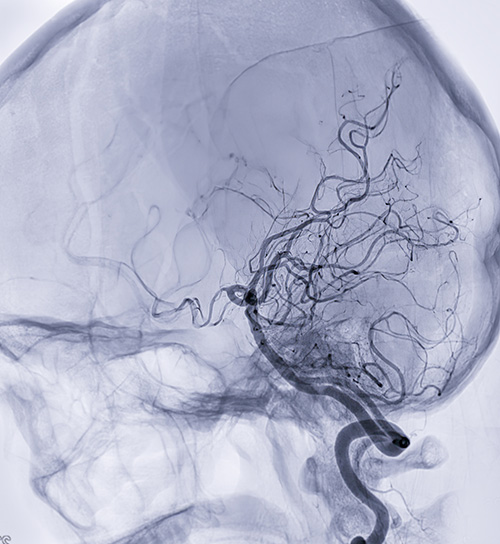

Researchers studied the growth patterns of the brain's vasculature, or cells, genes and pathways, to better understand the progression of diseases such as brain tumours and brain vascular malformations. (Photo: iStock)

In this study, researchers isolated blood vessels from human early developing brains, adult brains, brain tumours and brain vascular malformations. They found that endothelial cells, which line the blood vessels and regulate interactions between the bloodstream and surrounding tissues, behave differently across various stages of brain development, and may have a more important role than previously understood within the brain's neurovascular signaling networks.

• Researchers found that the vasculature in an adult healthy brain stops growing almost completely over time, but a brain tumour or a brain vascular malformation can reactivate blood vessel growth in the brain tissue, similar to the blood vessel growth in an early developing brain. This finding has never been described before.